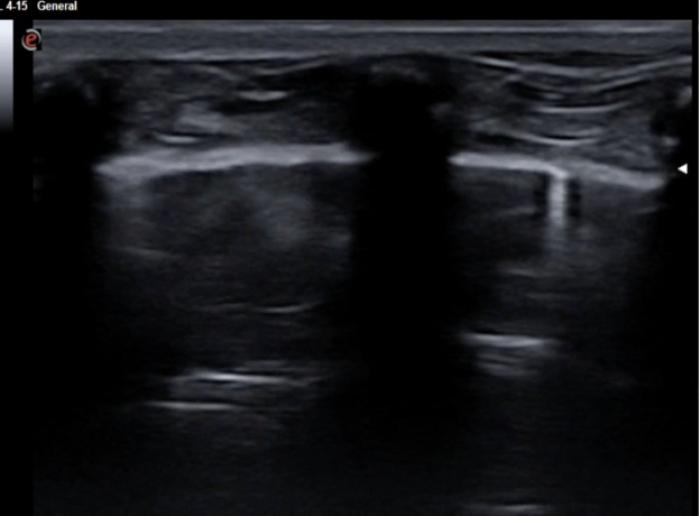

Líneas B

Se describen como líneas verticales que surgen de la línea pleuropulmonar y se extienden hasta el fondo del campo borrando las líneas A horizontales. El grosor de dichas líneas B puede variar y por ello podemos tener inclusive líneas coalescentes generando una imagen de “pulmón blanco”.

En los casos 1,2 y 3 hablaremos de líneas B húmedas y en los supuestos 4,5 y 6 de líneas B secas (Figura 4 y 5A-D).

La presencia de líneas B a menudo es el primer signo de anormalidad pulmonar detectado en la ecografía POCUS torácica no cardíaca.

En cuanto al número de dichas líneas se ha admitido que hasta 3 en un hemitórax se pueden visualizar en pacientes sanos, pero en opinión de esta autora, quizá este número sea demasiado elevado e infravalora una posible alteración pulmonar que aún no ha afectado a la superficie pleural.